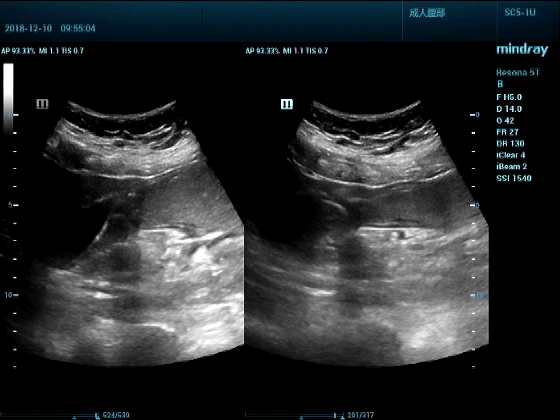

男,81岁,全身浮肿来住院

超声可见:左房,右房,右室明显增大,主肺动脉及右肺动脉增宽,二尖瓣中度反流,三尖瓣重度反流,肺动脉轻度高压,心律不齐

心包积液盆腔积液。淤血性肝增大,肝静脉增宽。(右心衰声像改变)